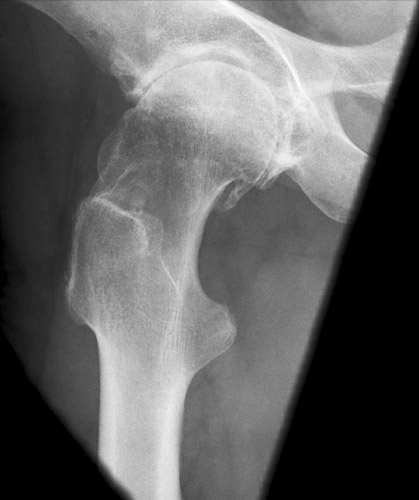

Lauenstein

118_3.jpg

Fehler

Der distale Schenkelhalsteil wird durch den Trochanter major verdeckt, wobei aber der mediale gelegene Abschnitt relativ frei ist. Außerdem ragt der Trochanter minor besonders markant und in ganzer Ausdehnung hervor und projiziert sich weit distal vom Trochanter major. Diese Fehleinstellung kommt vor allem bei Menschen mit schweren arthrotischen Knochenwülsten (Coxarthrosis deformans) am Hüftgelenk vor.

Abhilfe

Der Patient konnte zwar seinen Oberschenkel abspreizen, aber offenbar nur ungenügend; er drehte daher das Bein stark nach außen, was den Trochanter minor auf dem Bild mächtig hervorragen ließ.